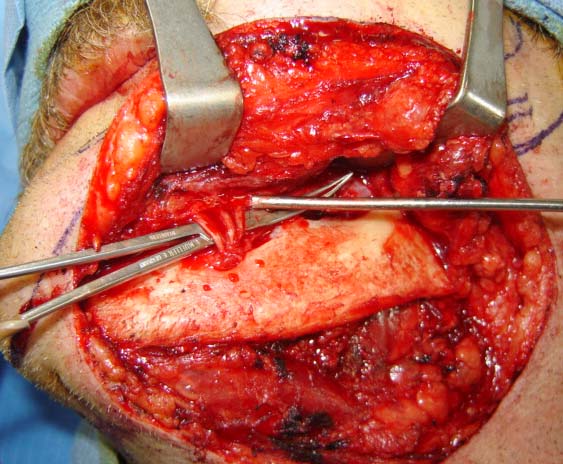

Head and Neck Tumor and Reconstruction

(cancer reconstruction)

Often after a patient has gone through various treatments for cancer there is a need that oral and maxillofacial services can provide for. In many cases, reconstructive surgery benefits patients having gone through specific skin cancers that are typically found in and around the head and neck regions. Depending on the severity and location of the cancer, skin cancer reconstruction options can range from simple to advanced procedures in order to restore both function and form.

The photos on this website are from real surgeries performed by Dr. Ulloa. Due to the

graphic nature of the images and content, viewer discretion is advised.